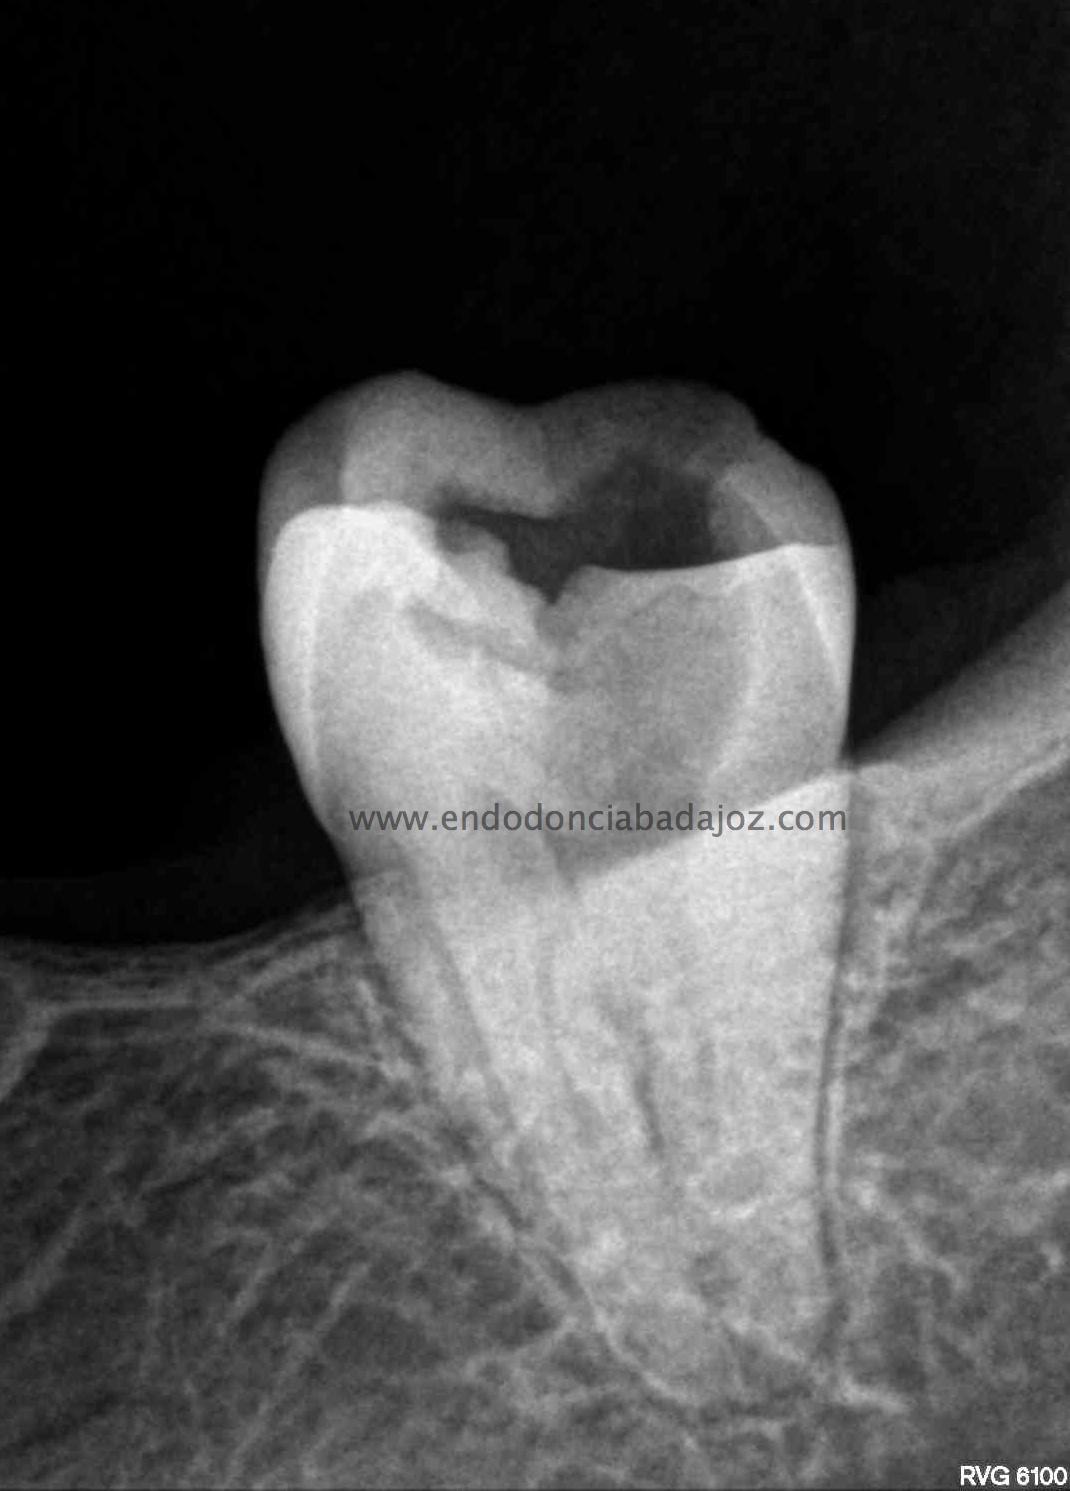

Se trata de un par de molares inferiores con lesiones apicales (Periodontitis apicales crónicas ). Consecuencia de caries profundas en su momento.

Se tratan del caso A y el caso B, por orden de posición, ambos casos se instrumentaron de la misma manera, elegimos Protaper hasta una F2, ambos casos se realizaron en una sesión tras abundante irrigación y finalmente se obturaron con condensación Vertical con la técnica de Ola continua de Buchanan complementando en el backfilling con guatpercha inyectada con la Pistola Obtura II.

Caso A:

Llamamos a la paciente a revisión a los 10 meses:

Caso B:

También se llamo a revisión a los 10 meses.